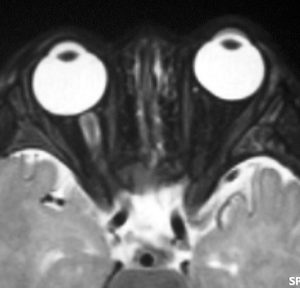

幼児の視路の毛様粘液性星細胞腫です。T2強調画像(左側)で白く高信号に写るのが特徴です。ガドリニウム増強ではまだらになっていますが,均一に真っ白に高信号になることも多いです。乳幼児のものは,ドロドロに柔らかい腫瘍です。

whole optic pathway pilocytic astrocytomaとは

両側の眼窩内視神経から視交叉、視索,外側膝状体,内包後脚,視放線近位部までが腫瘍化しています。FLAIRで高信号で,不規則にガドリニウム増強されます。これを手術摘出したり生検したりしても無駄です。放射線治療は不可能であり治療方法は化学療法のみです。

生後7カ月の幼児です。目が揺れるようになり(振り子様眼振)眼科を受診して腫瘍が発見されました。小児脳腫瘍の治療ができる病院へと紹介されました。

1ヶ月後にまたMRI検査がされました。乳児ですから検査にも麻酔が必要です。腫瘍は明らかに大きくなっています。左視神経から視索の腫瘍化が著しいので右側だけかすかに視力が残っているかもしれません。視力は明かりがわかる程度(明暗弁)と評価されました。